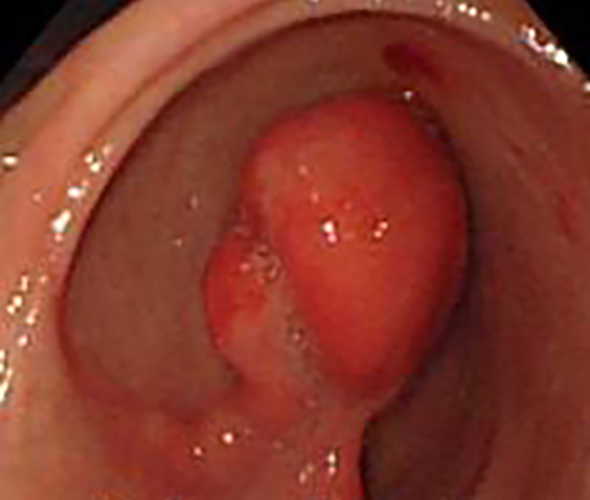

增生性胃息肉

增生性胃息肉常見症狀

增生型胃息肉